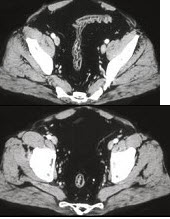

男,41岁,腹痛、腹泻、腹胀、脓血便、里急后重、疲乏无力,结合图像,选择最可诊断( )

A:溃疡性结肠炎

B:结肠克罗恩病

C:结肠结核

D:假膜性肠炎

E:结肠淋巴瘤